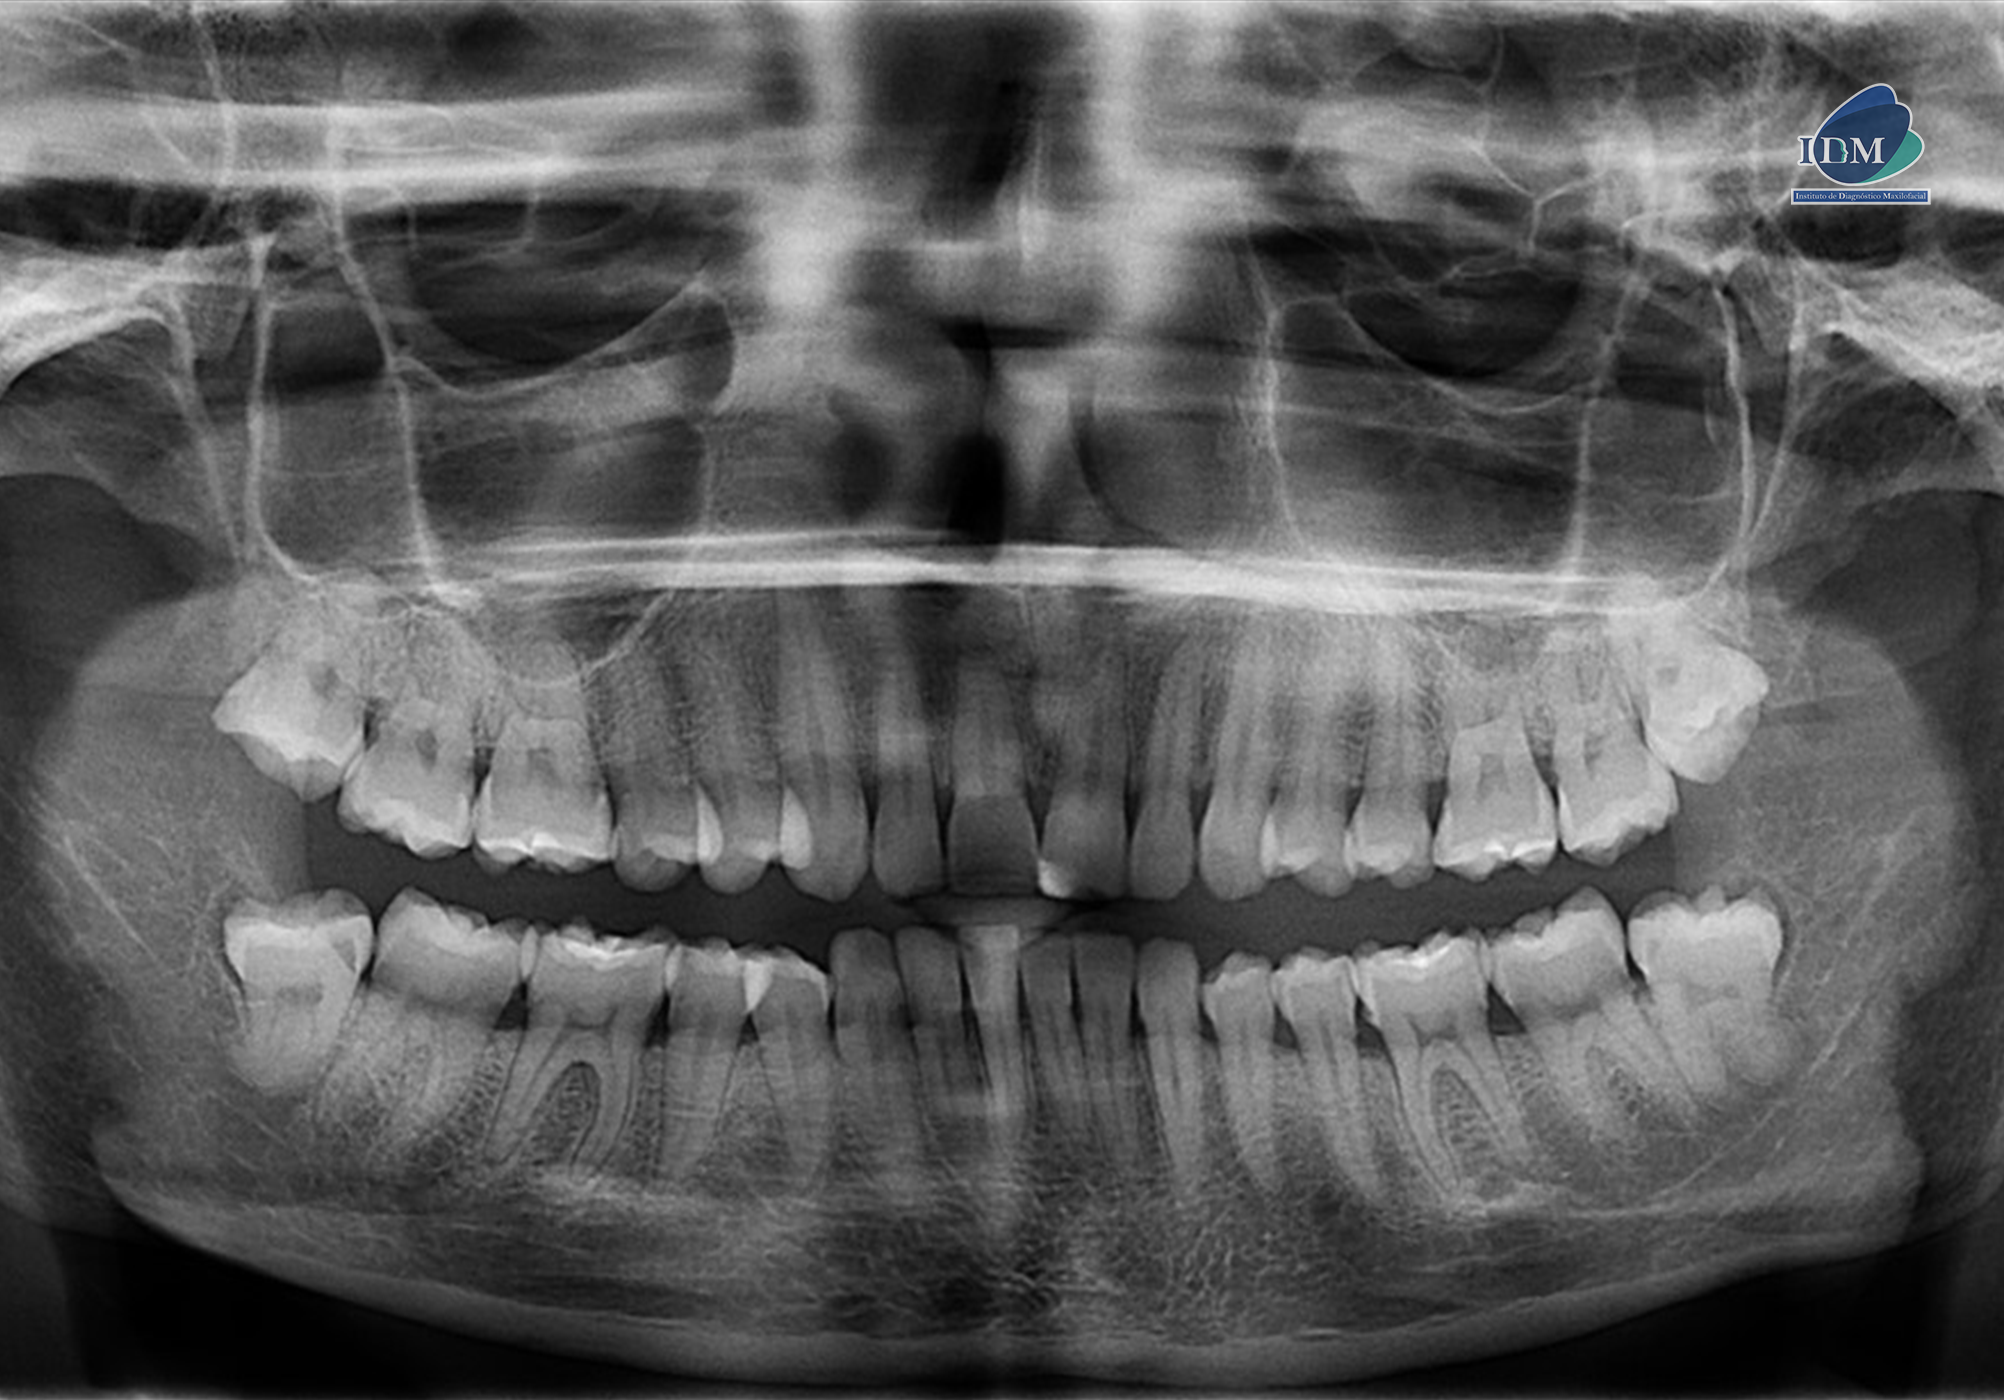

En la radiografía panorámica (Figura 1), se observa pieza 33 con pérdida del lumen del conducto radicular a nivel del tercio medio y apical.

Radiografia Panorámica